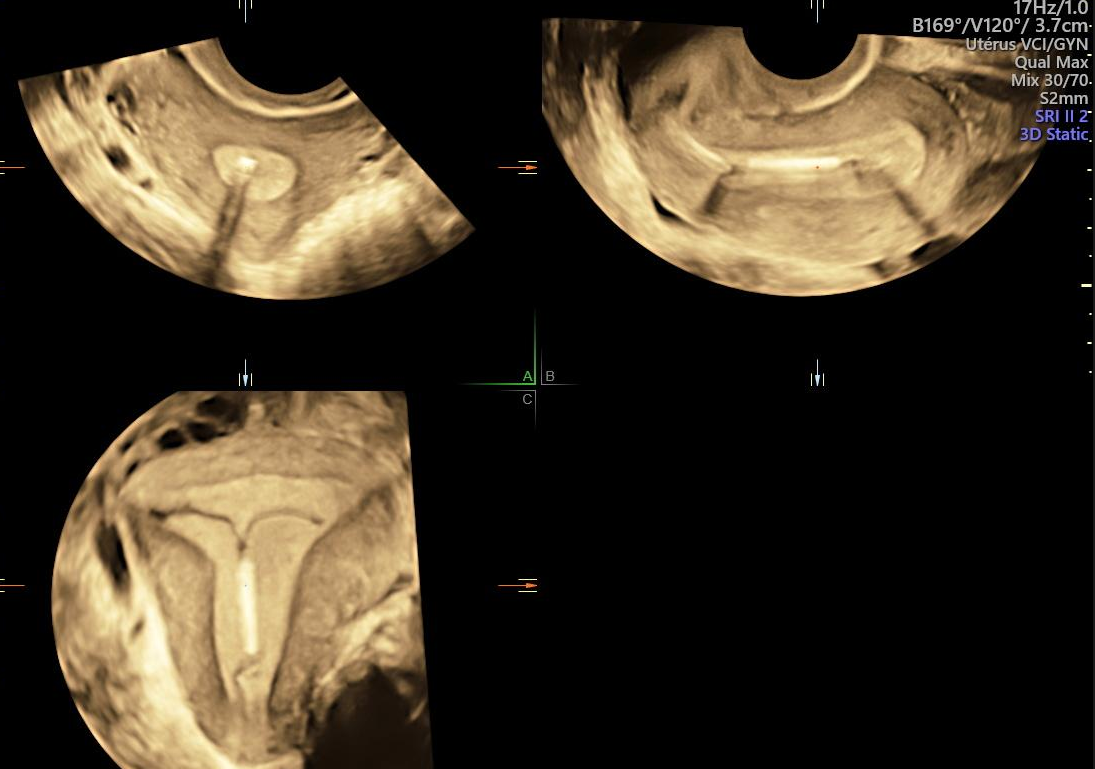

Retrait Mirena Et Après. Le stérilet Mirena sous surveillance après de nombreuses plaintes d'utilisatrices Femme Sand - 29 mai 2020 à 23:35 joraline - 29 mai 2020 à 23:40 Quel effet après retrait stérilet Mirena ? L'insertion ou le retrait de MIRENA peut provoquer des douleurs ou des saignements

Le stérilet hormonal Mirena, accusé de provoquer des effets secondaires Sciences et Avenir. Un malaise, parfois associé à une perte de connaissance (syncope) ou des convulsions (chez les épileptiques) peuvent également survenir lors de l'insertion. Retrait stérilet mirena après 50 ans - Meilleures réponses; Forum mirena et ménopause - Meilleures réponses; Poppers effet - Accueil - Drogues ;

Mirena IUD After Menopause Is it the same as Progesterone? YouTube. Cependant, il existe des avis partagés sur leur efficacité, leurs risques et les effets secondaires associés, notamment après le retrait Si une grossesse n'est pas souhaitée, MIRENA doit être retiré dans les 7 jours suivant le début des règles, à condition que la femme ait des cycles réguliers.